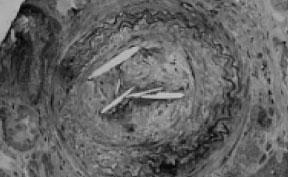

1.光镜检查 可见到肾脏血管和肾小球病变。动脉腔多闭塞并含有细胞成分,其中主要包括组织巨噬细胞和多形核白细胞。肾小动脉内有胆固醇结晶,可形成大量的胆固醇栓塞。典型者在弓形动脉、叶间动脉甚至终末端小动脉可以见到胆固醇结晶造成的人工假象,表现为细长的晶体形状的空间(见图5—9)。这是由于在组织固定时胆固醇被有机溶剂溶解或脱落所致。而电镜切片则由于处理方法不同可保留脂质成分。

图5—9 肾活检示:叶间动脉阻塞,胆固醇结晶表现为透明的裂隙